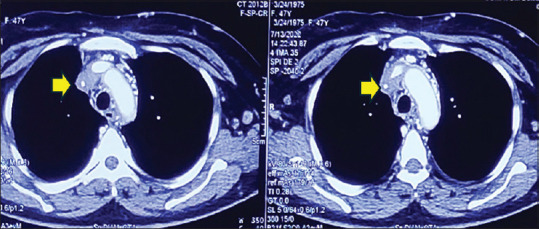

组织胞浆菌病表现为纤维化性纵隔炎和上腔静脉阻塞。

Histoplasmosis presenting as fibrosing mediastinitis and superior vena cava obstruction.